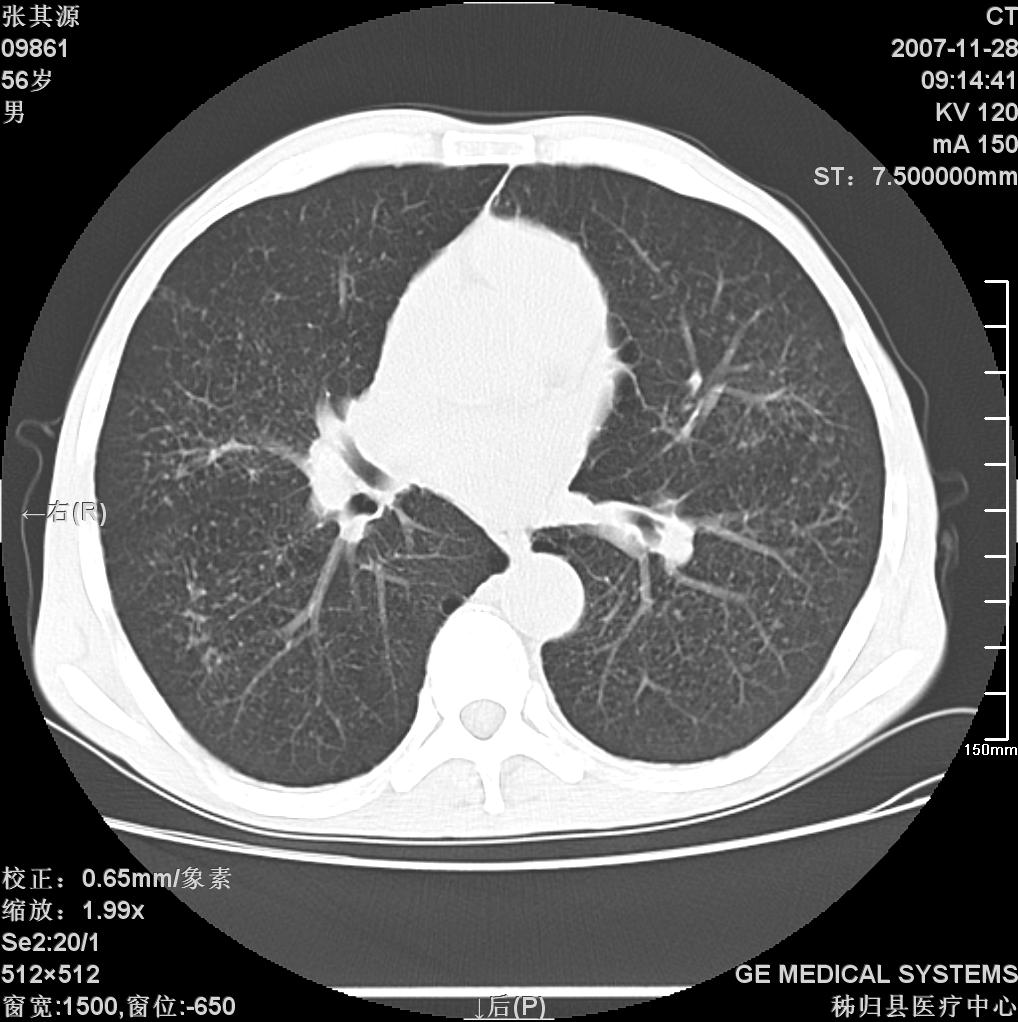

患者因阻塞性黄疸入院,发病前10天持续中等程度发烧.术前检查发现两肺弥漫性病变,请各位大虾会诊,除了考虑急性血源性肺结核外,还有其他什么疾病可能.

补充一下,该患者没有与尘肺相关职业史。请大家帮忙会诊一下,外科医生打算为其做胆总管肿瘤做手术的,现在在等我们的结果。谢谢各位了。

考虑tb不排除转移,(隆突处有肿大淋巴结,不好说是结核还是转移引起的)

双肺多发粟粒样病灶,右肺胸膜下结节样病灶,气管前腔静脉后及隆突下均见肿大淋巴结,结合胆道肿瘤病史首先考虑转移。另外心影密度略低,时间格显示,是否有贫血?查明白再手术吧!